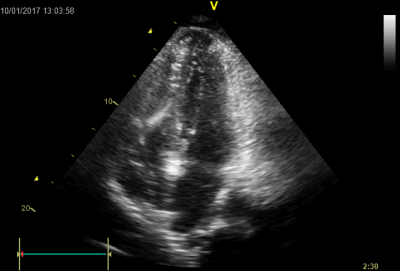

Video 1 - Akutní koronarografie prokázala normální nález na věnčitých tepnách s výjimkou suspekce na lehký spasmus na pravé koronární tepně.Echokardiograficky byla zjištěna těžká dysfunkce dilatované levé komory s nezvětšenou pravou komorou (video 2).

Na kůži byl nápadný, v čase proměnlivý hnědočervený makulopapulózní exantém s převahou na předních a laterálních partiích stehen a na podbřišku, pro který byla nemocná vyšetřována již v minulosti bez jasného výsledku. Koncentrace tryptázy v séru v kontrolních odběrech byla překvapivě zvýšena nadále i v odstupu několika dnů (tabulka 2), ačkoliv při anafylaxi jsou hodnoty zvýšeny pouze v období do čtyř až šesti hodin. Vzhledem k suspektnímu dermatologickému nálezu, který imponoval jako urticaria pigmentosa, a ke zvýšení bazální tryptázy padlo podezření na systémovou mastocytózu. Zahájili jsme proto příslušnou léčbu antihistaminiky (levocetirizin). Stav se postupně zlepšoval a šestý den hospitalizace jsme pacientku extubovali, nedošlo k poškození mozku (cerebral performance category scale 1 [CPC-1]) a při současné terapii milrinonem se zlepšila i ejekční frakce levé komory z 25 % na 55 % (video 2–4); dobrá funkce levé komory přetrvávala i po vysazení inotropik.